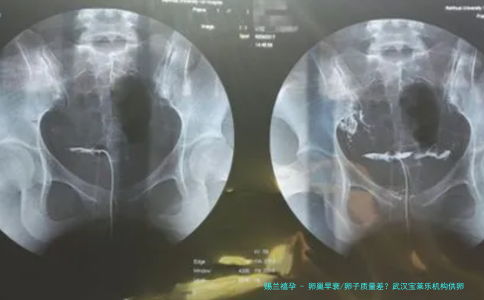

在现代社会, 卵巢早衰 卵子质量差 已成为越来越多育龄女性面临的生育难题。据统计,我国卵巢早衰的发病率约为1%-3%,且呈现年轻化趋势。对于这些女性而言,自然怀孕的几率大幅降低,而试管婴儿技术成为了她们实现生育梦想的重要途径。然而,当自身卵子质量或数量无法满足试管需求时, 供卵试管婴儿 便成为了一个备受关注的选项。武汉作为华中地区的医疗中心,拥有众多辅助生殖机构,其中 武汉宝莱乐机构 因其专业的供卵试管服务而受到部分患者的关注。那么,对于卵巢早衰或卵子质量差的女性来说,武汉宝莱乐机构真的是理想选择吗?本文将从多个维度为您深入分析。